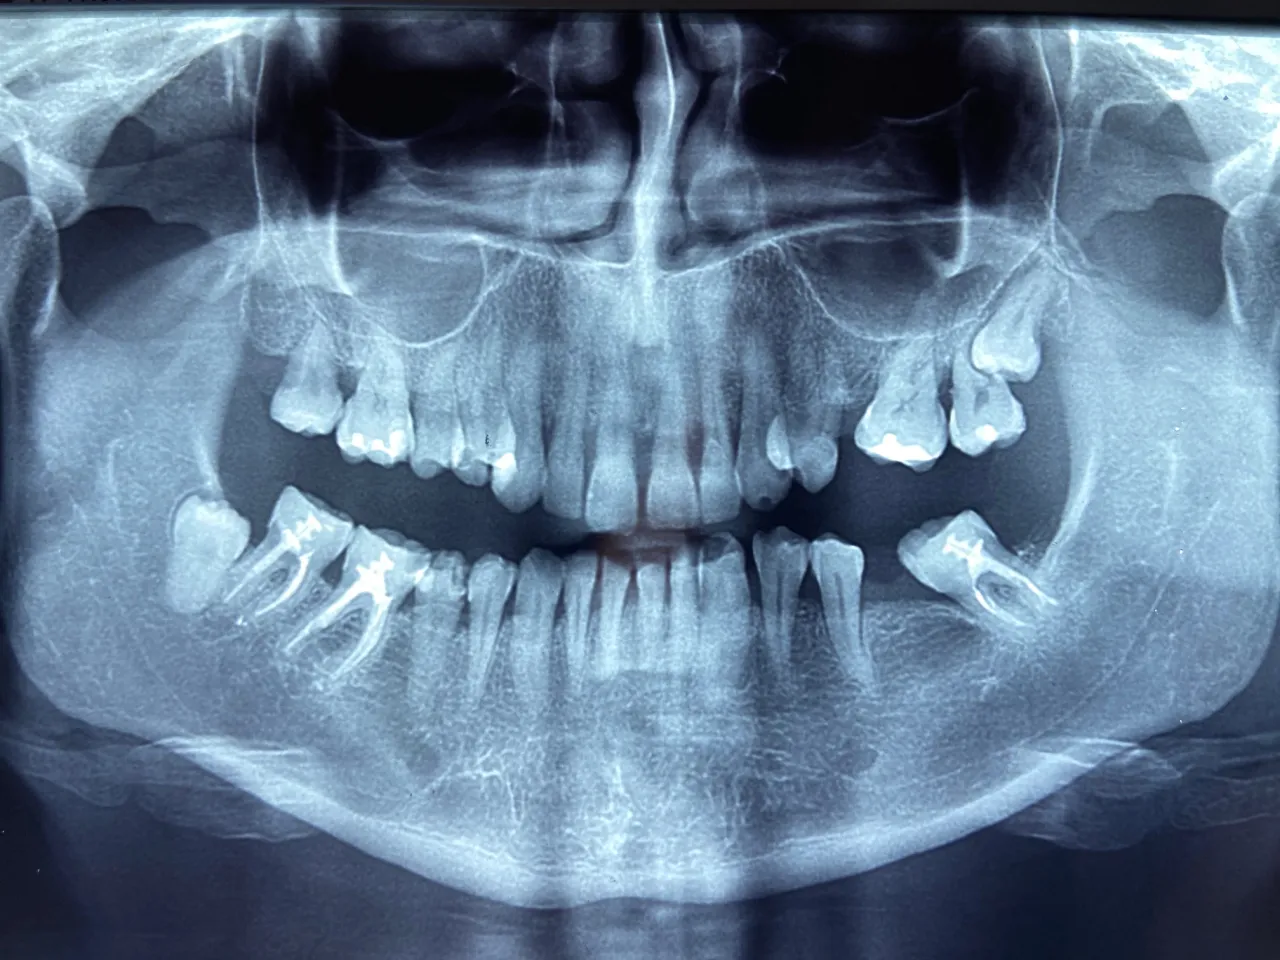

Zęby mądrości, czyli ósemki, to ostatnie zęby w łuku zębowym. Ich wyrzynanie to często temat wielu dyskusji i problemów. Zazwyczaj pojawiają się między 17. a 25. rokiem życia, choć proces ten jest bardzo indywidualny i może trwać latami, a czasem ósemki w ogóle się nie wyrzynają. W dolnej szczęce możemy mieć dwie ósemki po jednej z każdej strony. Ich obecność jest zmienna, co oznacza, że nie każdy ma wszystkie cztery, a niektórzy nie mają ich wcale.

Dolne zęby mądrości często bywają problematyczne. Ze względu na to, że wyrzynają się jako ostatnie, w żuchwie często brakuje dla nich miejsca. To prowadzi do wielu komplikacji, takich jak nieprawidłowy kąt wzrostu ósemka może rosnąć poziomo, uciskając sąsiednie zęby, lub częściowo wychodzić z dziąsła. Taka sytuacja często powoduje silny ból, stany zapalne dziąseł wokół zęba (tzw. pericoronitis) oraz stłoczenia innych zębów, co może zrujnować efekty leczenia ortodontycznego. W wielu przypadkach, aby zapobiec tym problemom lub je rozwiązać, konieczne jest usunięcie ósemek. To właśnie dlatego ostateczna liczba zębów w żuchwie dorosłego człowieka tak często wynosi 14, a nie 16.

Co to jest zatrzymany ząb mądrości w żuchwie?

Pojęcie "zatrzymany ząb mądrości" odnosi się do ósemki, która z różnych przyczyn nie jest w stanie prawidłowo wyrznąć się w jamie ustnej. W żuchwie jest to szczególnie częste zjawisko. Ząb może być częściowo zatrzymany, co oznacza, że tylko fragment korony jest widoczny ponad dziąsłem, lub całkowicie zatrzymany, gdy pozostaje on w całości ukryty pod dziąsłem i kością. Zatrzymane ósemki są często źródłem bólu, infekcji i innych problemów stomatologicznych.